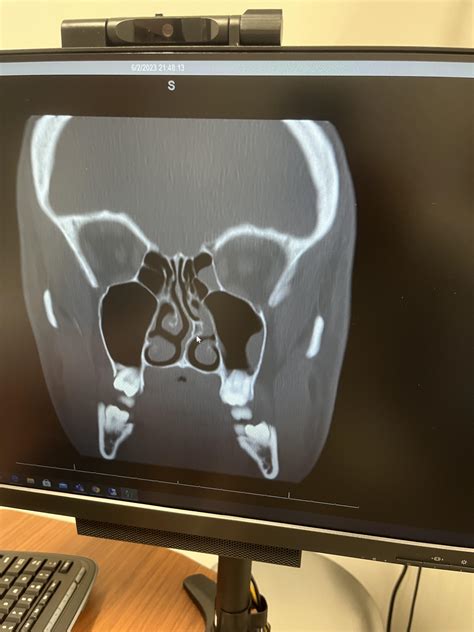

Once the images are captured, they are processed by a radiologist. The radiologist looks for specific markers of health or disease. They will examine the sinus ostia (the small openings where sinuses drain) to see if they are blocked by polyps or mucosal swelling. They will also look for opacification—a term used when the typically air-filled sinuses appear white or gray on the image, indicating they are filled with fluid, mucus, or thickened tissue.

Your ENT specialist will then combine these findings with your clinical symptoms to form a diagnosis. It is important to remember that a scan alone is not a diagnosis; it is one piece of the puzzle. A clear sinus scan in a patient with chronic symptoms may indicate that the problem is not related to structural sinus issues but perhaps to something else, such as allergies or environmental triggers.

Selecting the Right Facility

Not all imaging centers are equal. When choosing where to get your Ct scans sinus, consider asking about the age and capability of their equipment. Many modern ENT clinics have "in-office" CT scanners designed specifically for sinus and ear imaging. These are often more convenient for patients and allow for an immediate consultation with your doctor regarding the results, rather than waiting days for a report from a remote hospital facility.